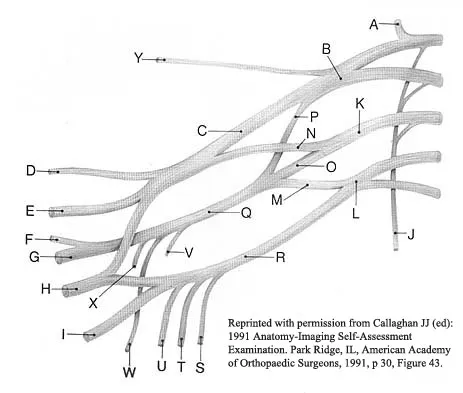

A patient who sustained a knife wound to the axilla 4 months ago now has profound interosseous wasting and generalized hand weakness. A brachial plexus injury is likely at which of the following locations in Figure 29?

The primary function of structure "A" in Figure 29 is to limit